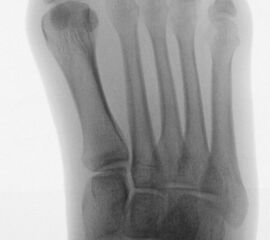

In der Regel bestehen aktive Wachstumsfugen bei Mädchen bis zum 12. und bei Jungen bis zum 14. Lebensjahr, mit Abweichungen von einem Jahr nach unten und nach oben. Präzise Informationen unter anderem darüber gibt das präoperative Röntgenbild (Abb. 2).

Abb. 2 a-c: offene Wachstumsfugen MT I Basis und Zehen (a), teilweise geöffnete Wachstumsfugen (b) und geschlossene Wachstumsfugen (c).